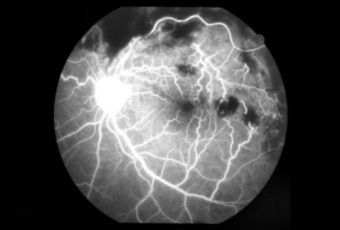

CENTRAL RETINAL VEIN OCCLUSION (CRVO) |

The actual mechanisms producing the clinical picture of central retinal vein occlusion may be roughly divided into those conditions that produce a physical blockage at the level of the lamina cribrosa, and those conditions in which hemodynamic factors result in an obstruction to the flow of blood. These mechanisms probably coexist in many patients with Central Vein Occlusion.

Confluent hemorrhages are the most prominent ophthalmoscopic feature of an acute ischemic central retinal vein occlusion These hemorrhages occur in a wide variety of shapes and sizes; they are usually concentrated in the posterior pole, but may be seen throughout the retina. Many hemorrhages are flame shaped, reflecting the orientation of the nerve fibers. Dot and punctate hemorrhages are interspersed and indicate involvement of the deeper retinal layers. Bleeding may be extensive, erupting through the internal limiting membrane to form a preretinal hemorrhage or extending into the vitreous. Small dot hemorrhages may be seen either isolated or clustered around small venules. The entire venous tree is tortuous, engorged, dilated, and dark. The retina is edematous, particularly in the posterior pole; some of this edema may obscure portions of the retinal vessels. Cotton-wool patches (soft exudates) are often present. The disc margin is blurred or obscured, and the precapillary arterioles appear engorged. Splinter hemorrhages and edema are present on the disc surface and extend into the surrounding retina. The physiologic cup is filled, and the venous pulse is absent. The arterioles, often overlooked because of the other more striking pathologic features, are frequently narrowed. Sometimes in central retinal vein occlusion of acute onset, the fundus picture is less dramatic, and all of the findings previously discussed may be present, but to a lesser degree. Vision depends on extent of macular involvement